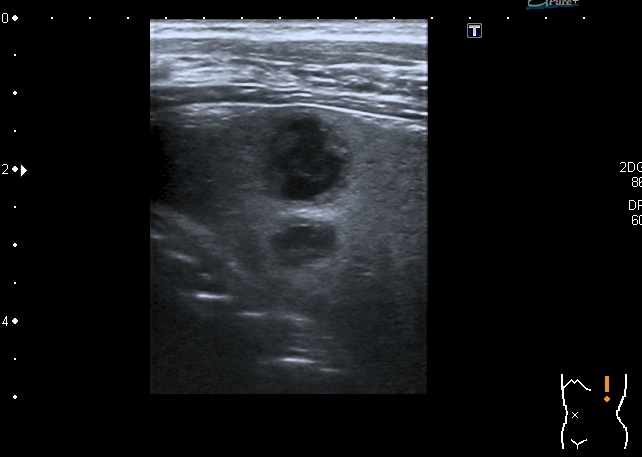

"Плохой"  подмышечный лимфатический узел, но справа. "Bad" axillar LN is seen

The irregularity of the rib shown sonographically suggests an osseous process like Ewing sarcoma. However, I have seen three patients with similar findings with destruction of the sternum and adjacent ribs mimicking a tumour of the bone but caused by an infiltration of a Hodgkin’s lymphoma. A lymphoma would also be more consistent with the lesions found in the spleen. Regarding the morphology and shape of the mass in the axilla, I think this is a lymphnode.

In any case, I would recommend excluding a lymphoma in addition to Ewing sarcoma. Infiltration of the sternum or ribs caused by Mb. Hodgkin is an important differential diagnosis, which is also suggested by the splenic lesions in that case that are possible but not typical for Ewing sarcoma.